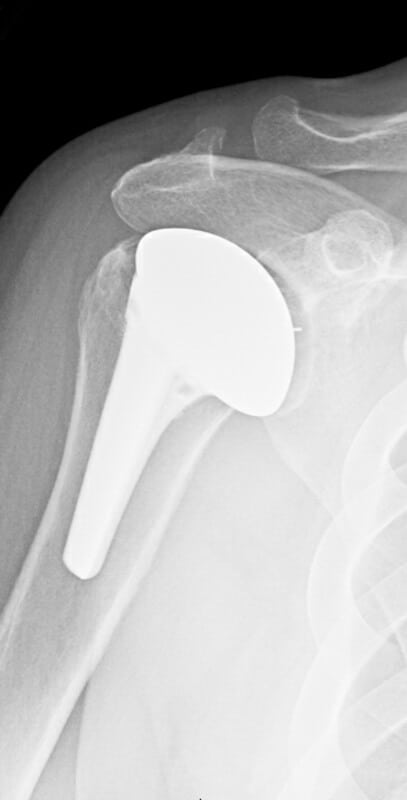

DePuy, Inhance